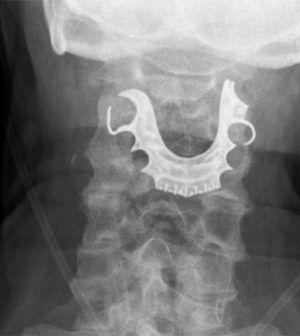

At this point, he was re-admitted to the hospital. Tests revealed a semi-circular object lying across his vocal cords, which had caused internal swelling and blistering.

When told this, the man said his dentures — a metal roof plate and three false teeth — were lost during his previous hospital stay for his abdominal surgery.